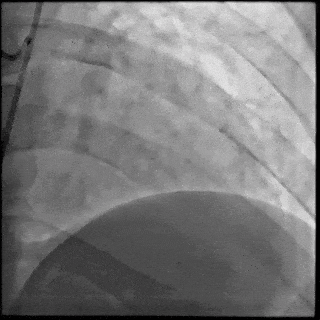

5月28日8:00,葛均波院士团队在中山医院16号楼16楼中伟厅成功连线喀什二院导管室,沪喀远程手术正式开始。8:35,新疆喀什二院导管室内股动脉入路通路建立后,行左右冠脉造影示左前降支中段存在85%的严重狭窄,狭窄位于血管分叉路口且紧邻心肌桥;且左回旋支中段近乎闭塞,血管细窄且迂曲,病变弥漫。8:59,葛院士于上海操控血管介入机器人主端,将指引导管送至左冠脉开口,并操控主支导丝和分支血管保护导丝通过狭窄病变,后送至前降支和对角支血管远端以建立轨道,同时利用介入机器人的微速调整功能避开心肌桥,以亚毫米级精准定位释放1枚支架。在成功处理患者左前降支病变后,葛院士通过搓捻机械操纵杆,远程精细调整导丝“进攻”方向,顺利通过左回旋支次全闭塞病变。因血管相对细小且病变弥漫,葛院士决定采用单纯球囊扩张术处理,即刻造影提示几乎无残余狭窄,避免了额外的支架植入。10:10,撤出所有导丝及导管,手术顺利结束。

【DSA图3.回旋支导丝顺利通过病变】